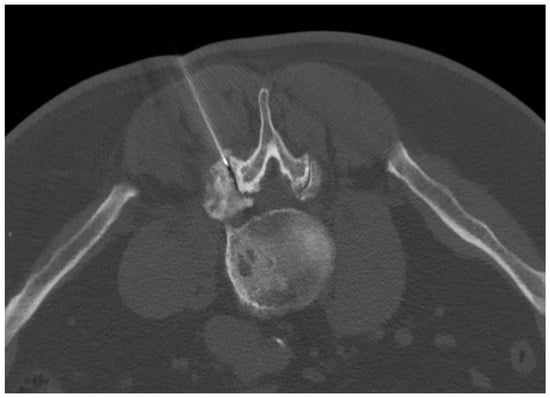

2.2.1. Intradiscal Approach

- Muto, M.; Avella, F. Percutaneous treatment of herniated lumbar disc by intradiscal oxygen-ozone injection. Interv. Neuroradiol. J. Perither. Neuroradiol. Surg. Proced. Relat. Neurosci. 1998, 4, 279–286. [Google Scholar] [CrossRef]

- Ezeldin, M.; Leonardi, M.; Princiotta, C.; Dall’olio, M.; Tharwat, M.; Zaki, M.; Abdel-Wanis, M.E.; Cirillo, L. Percutaneous Ozone Nucleolysis for Lumbar Disc Herniation. Neuroradiology 2018, 60, 1231–1241. [Google Scholar] [CrossRef] [PubMed]

- Giurazza, F.; Guarnieri, G.; Murphy, K.J.; Muto, M. Intradiscal O2O3: Rationale, Injection Technique, Short- and Long-term Outcomes for the Treatment of Low Back Pain Due to Disc Herniation. Can. Assoc. Radiol. J. 2017, 68, 171–177. [Google Scholar] [CrossRef] [PubMed]

- Muto, M.; Ambrosanio, G.; Guarnieri, G.; Capobianco, E.; Piccolo, G.; Annunziata, G.; Rotondo, A. Low Back Pain and Sciatica: Treatment with Intradiscal-Intraforaminal O(2)-O(3) Injection. Our Experience. Radiol. Med. 2008, 113, 695–706. [Google Scholar] [CrossRef]